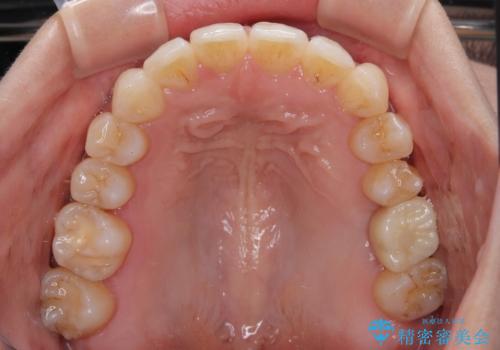

- 全体的なデコボコと、以前抜歯した歯のスペースを閉じた部分が気になるとのことで来院された患者様です。

左上第一大臼歯を抜歯した際に、スペースを閉じたそうですが、歯が傾斜してものが挟まって不快とのことでした。

インビザライン矯正で全体の歯列と整えるとともに、左上第一大臼歯部にはスペースを作り、インプラントによる補綴治療を行うこととしました。